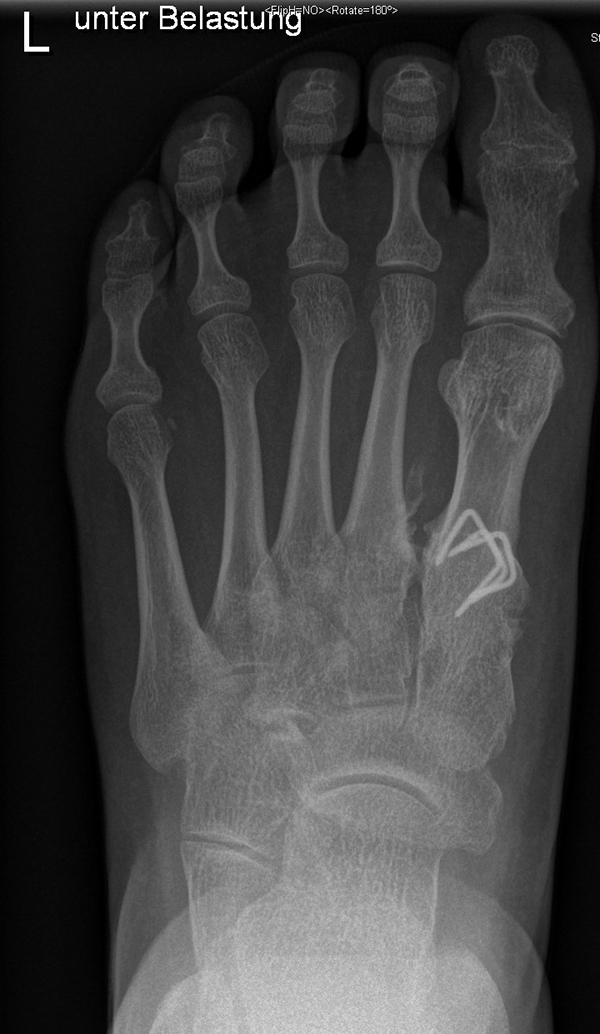

Diagnostisches Vorgehen

Damit die minimalinvasive Fußchirurgie zur Korrektur kindlicher oder jugendlicher Fußdeformitäten erfolgreich angewendet werden kann, erfordert die präoperative Diagnostik Röntgenbilder in drei Ebenen am stehenden Fuß. Röntgenbilder ohne Belastung des Fußes sind nicht zielführend. Im Fall von schweren Rückfußdeformitäten wird das obere Sprunggelenk in die radiologische Diagnostik mit einbezogen in Kombination mit der Rückfußaufnahme unter Belastung („Saltzman View“). Das OSG wird in zwei Ebenen geröntgt. Die streng seitliche Aufnahme des OSG kann bei den komplexen Fußdeformitäten mit der seitlichen Aufnahme des Fußes unter Belastung kombiniert werden. Das reduziert die diagnostische Strahlenbelastung der Kinder.

Indikationen für die beschriebenen Röntgenaufnahmen sind Klumpfußdeformitäten zur Beurteilung eines „flat top talus“ oder neurologische Grunderkrankungen mit varischer Fersenstellung wie zum Beispiel bei HSMN (Hereditäre Sensorische Motorische Neuropathie).